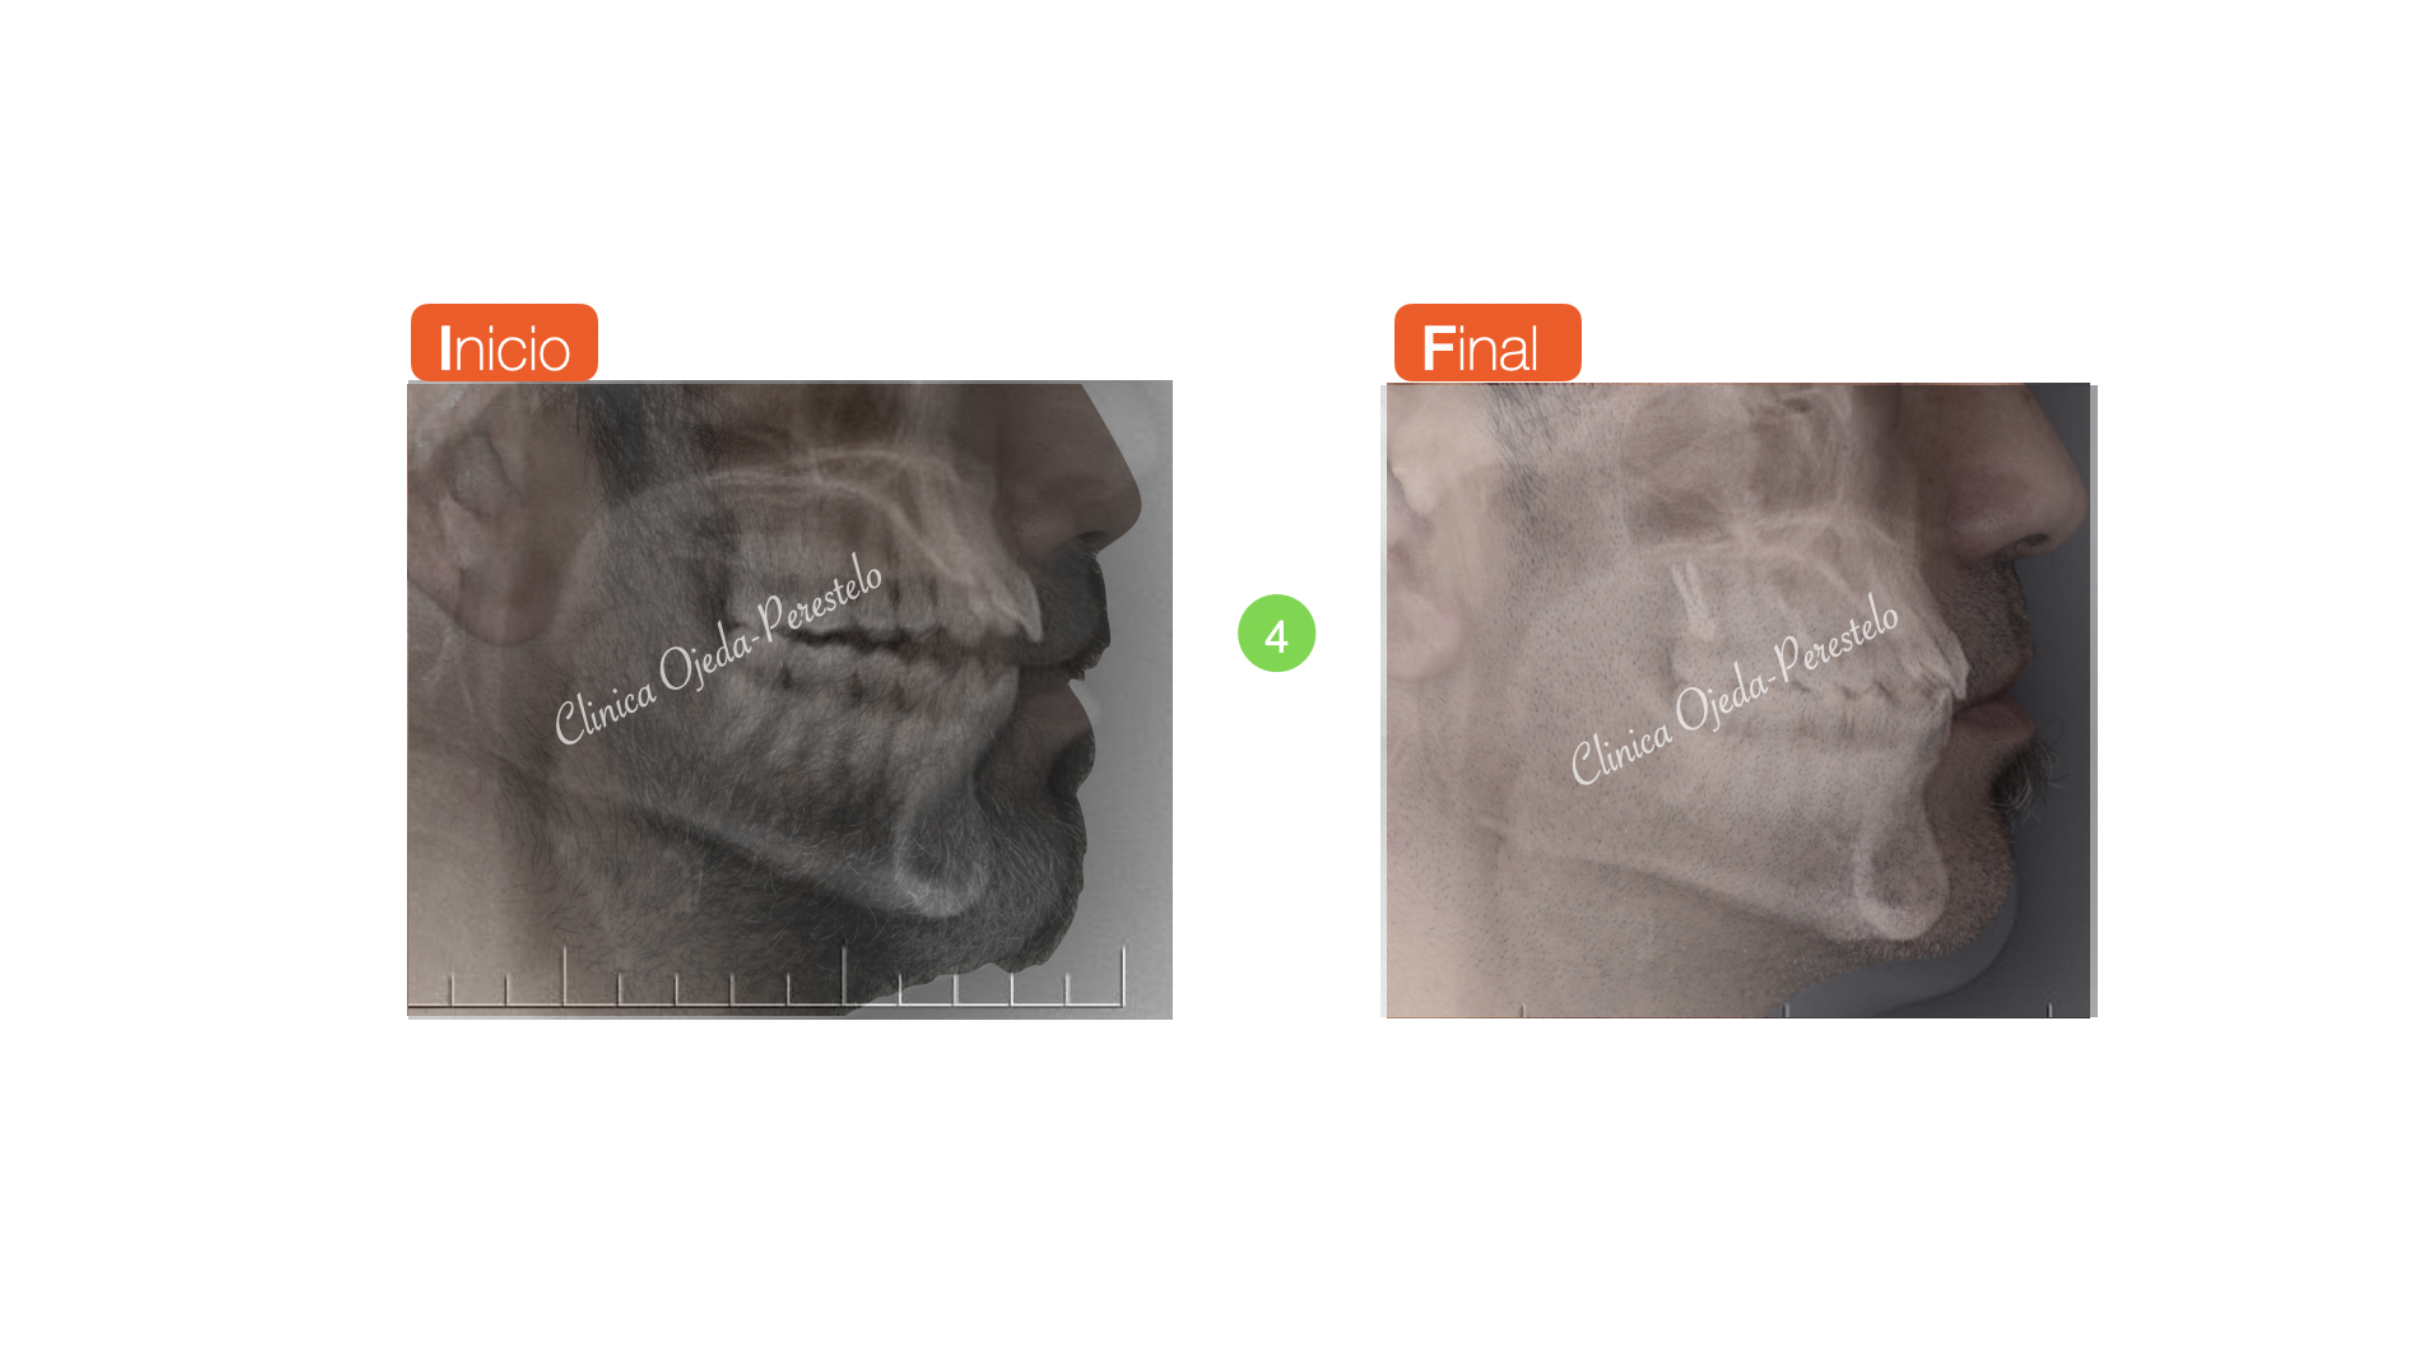

Mordida Abierta de molar a molar

Los alineadores son una excelente opción terapéutica en aquellos pacientes con mordida abierta. Presentamos un caso severo donde se realizó el cierre de la mordida con alineadores transparentes y Microtornillos combinado intrusión posterior con extrusión anterior. También realizamos el desarrollo transversal (expansión) de las arcadas.

Se ha alcanzado el objetivo con 34 alineadores Maxilares y 33 Mandibulares con cambio semanal en un tiempo de 8 meses y medio.